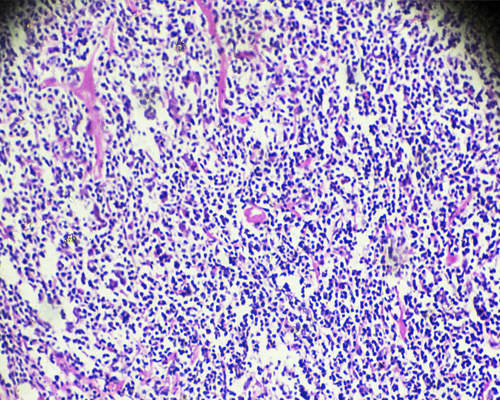

Los linfomas de Hodgkin constituyen uno de los 2 subgrupos principales de linfomas, de los que en España se diagnosticaron 1.193 nuevos casos en el año 2023, según las estimaciones del Observatorio del Cáncer de la Asociación Española Contra el Cáncer. Este tipo de linfoma se caracteriza por el hallazgo en los ganglios linfáticos de linfocitos de tipo B alterados que se conocen como células de Reed-Sternberg.

Tras una serie de pruebas realizadas en el laboratorio, se identificarán los tipos específicos de linfoma de Hodgkin clásico (hay 4 subtipos en la clasificación habitual de los hematólogos) o se realizará el diagnóstico de linfoma de Hodgkin de predominio linfocítico nodular. Estos son las dos variedades principales, ambas diferentes en su tratamiento y evolución.